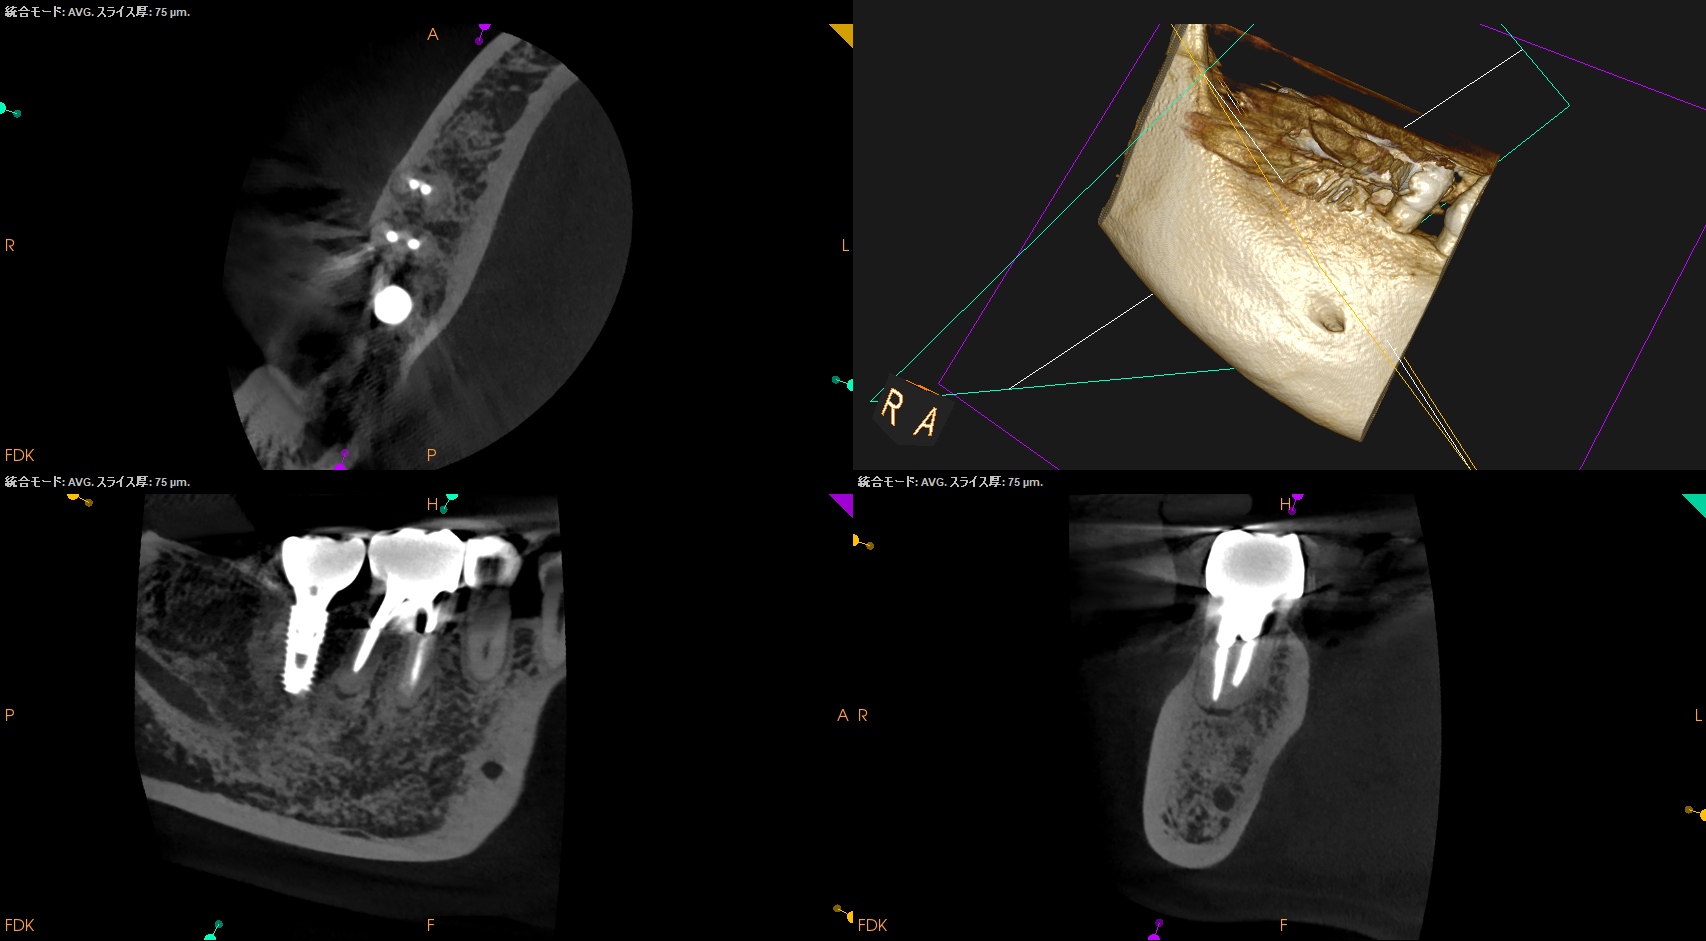

CBCT(2025.10.27)

MB

ML

DB

DL

MのApexに到達するにはCEJよりも12.5mm下方の歯槽骨を2mm削合(Osteotomy)しなければならない。

Apexを見つけたら3mm切断するがこの時の頬舌的な幅径が6.3mmだ。

リンデマンバーの半分よりも長い。

またDはApexに到達するには、CEJよりも13mm下方の歯槽骨を3mm削合する必要がある。

まさに…芋掘りだ。。。